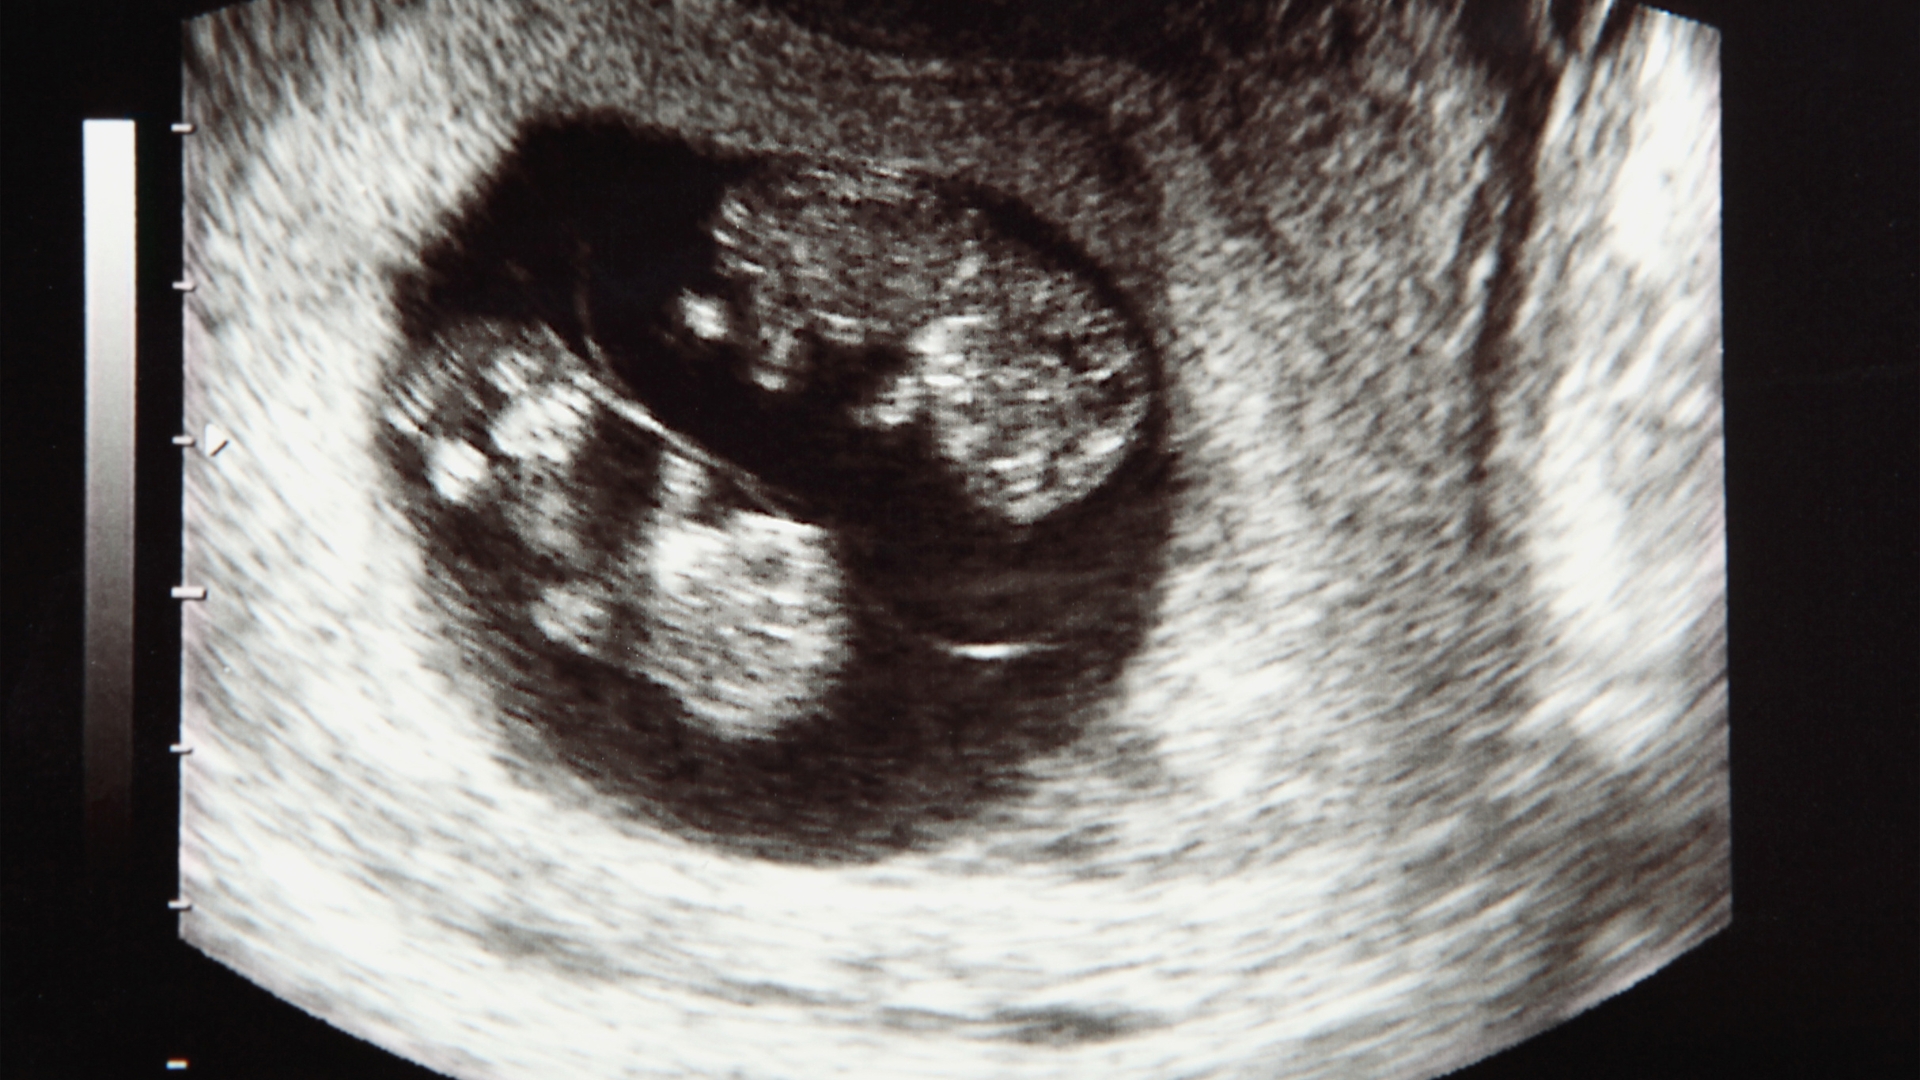

Song thai là hiện tượng trong đó có hai phôi thai cùng phát triển trong tử cung của người mẹ. Tình trạng này có thể hình thành do hai cơ chế khác nhau và thường được xác định trong tam cá nguyệt đầu tiên thông qua siêu âm:

Khi mang song thai, mẹ bầu cần được theo dõi chặt chẽ hơn nhằm phát hiện sớm các nguy cơ tiềm ẩn. Việc thăm khám định kỳ giúp đánh giá sự phát triển của cả hai thai nhi một cách toàn diện. Bác sĩ sẽ theo dõi chiều dài cổ tử cung và kiểm tra lượng nước ối đều đặn để phát hiện dấu hiệu dọa sinh non. Siêu âm thường xuyên là cần thiết để kịp thời phát hiện hội chứng truyền máu song thai hoặc tình trạng phát triển không đồng đều giữa hai bé, từ đó can thiệp sớm nếu cần thiết.